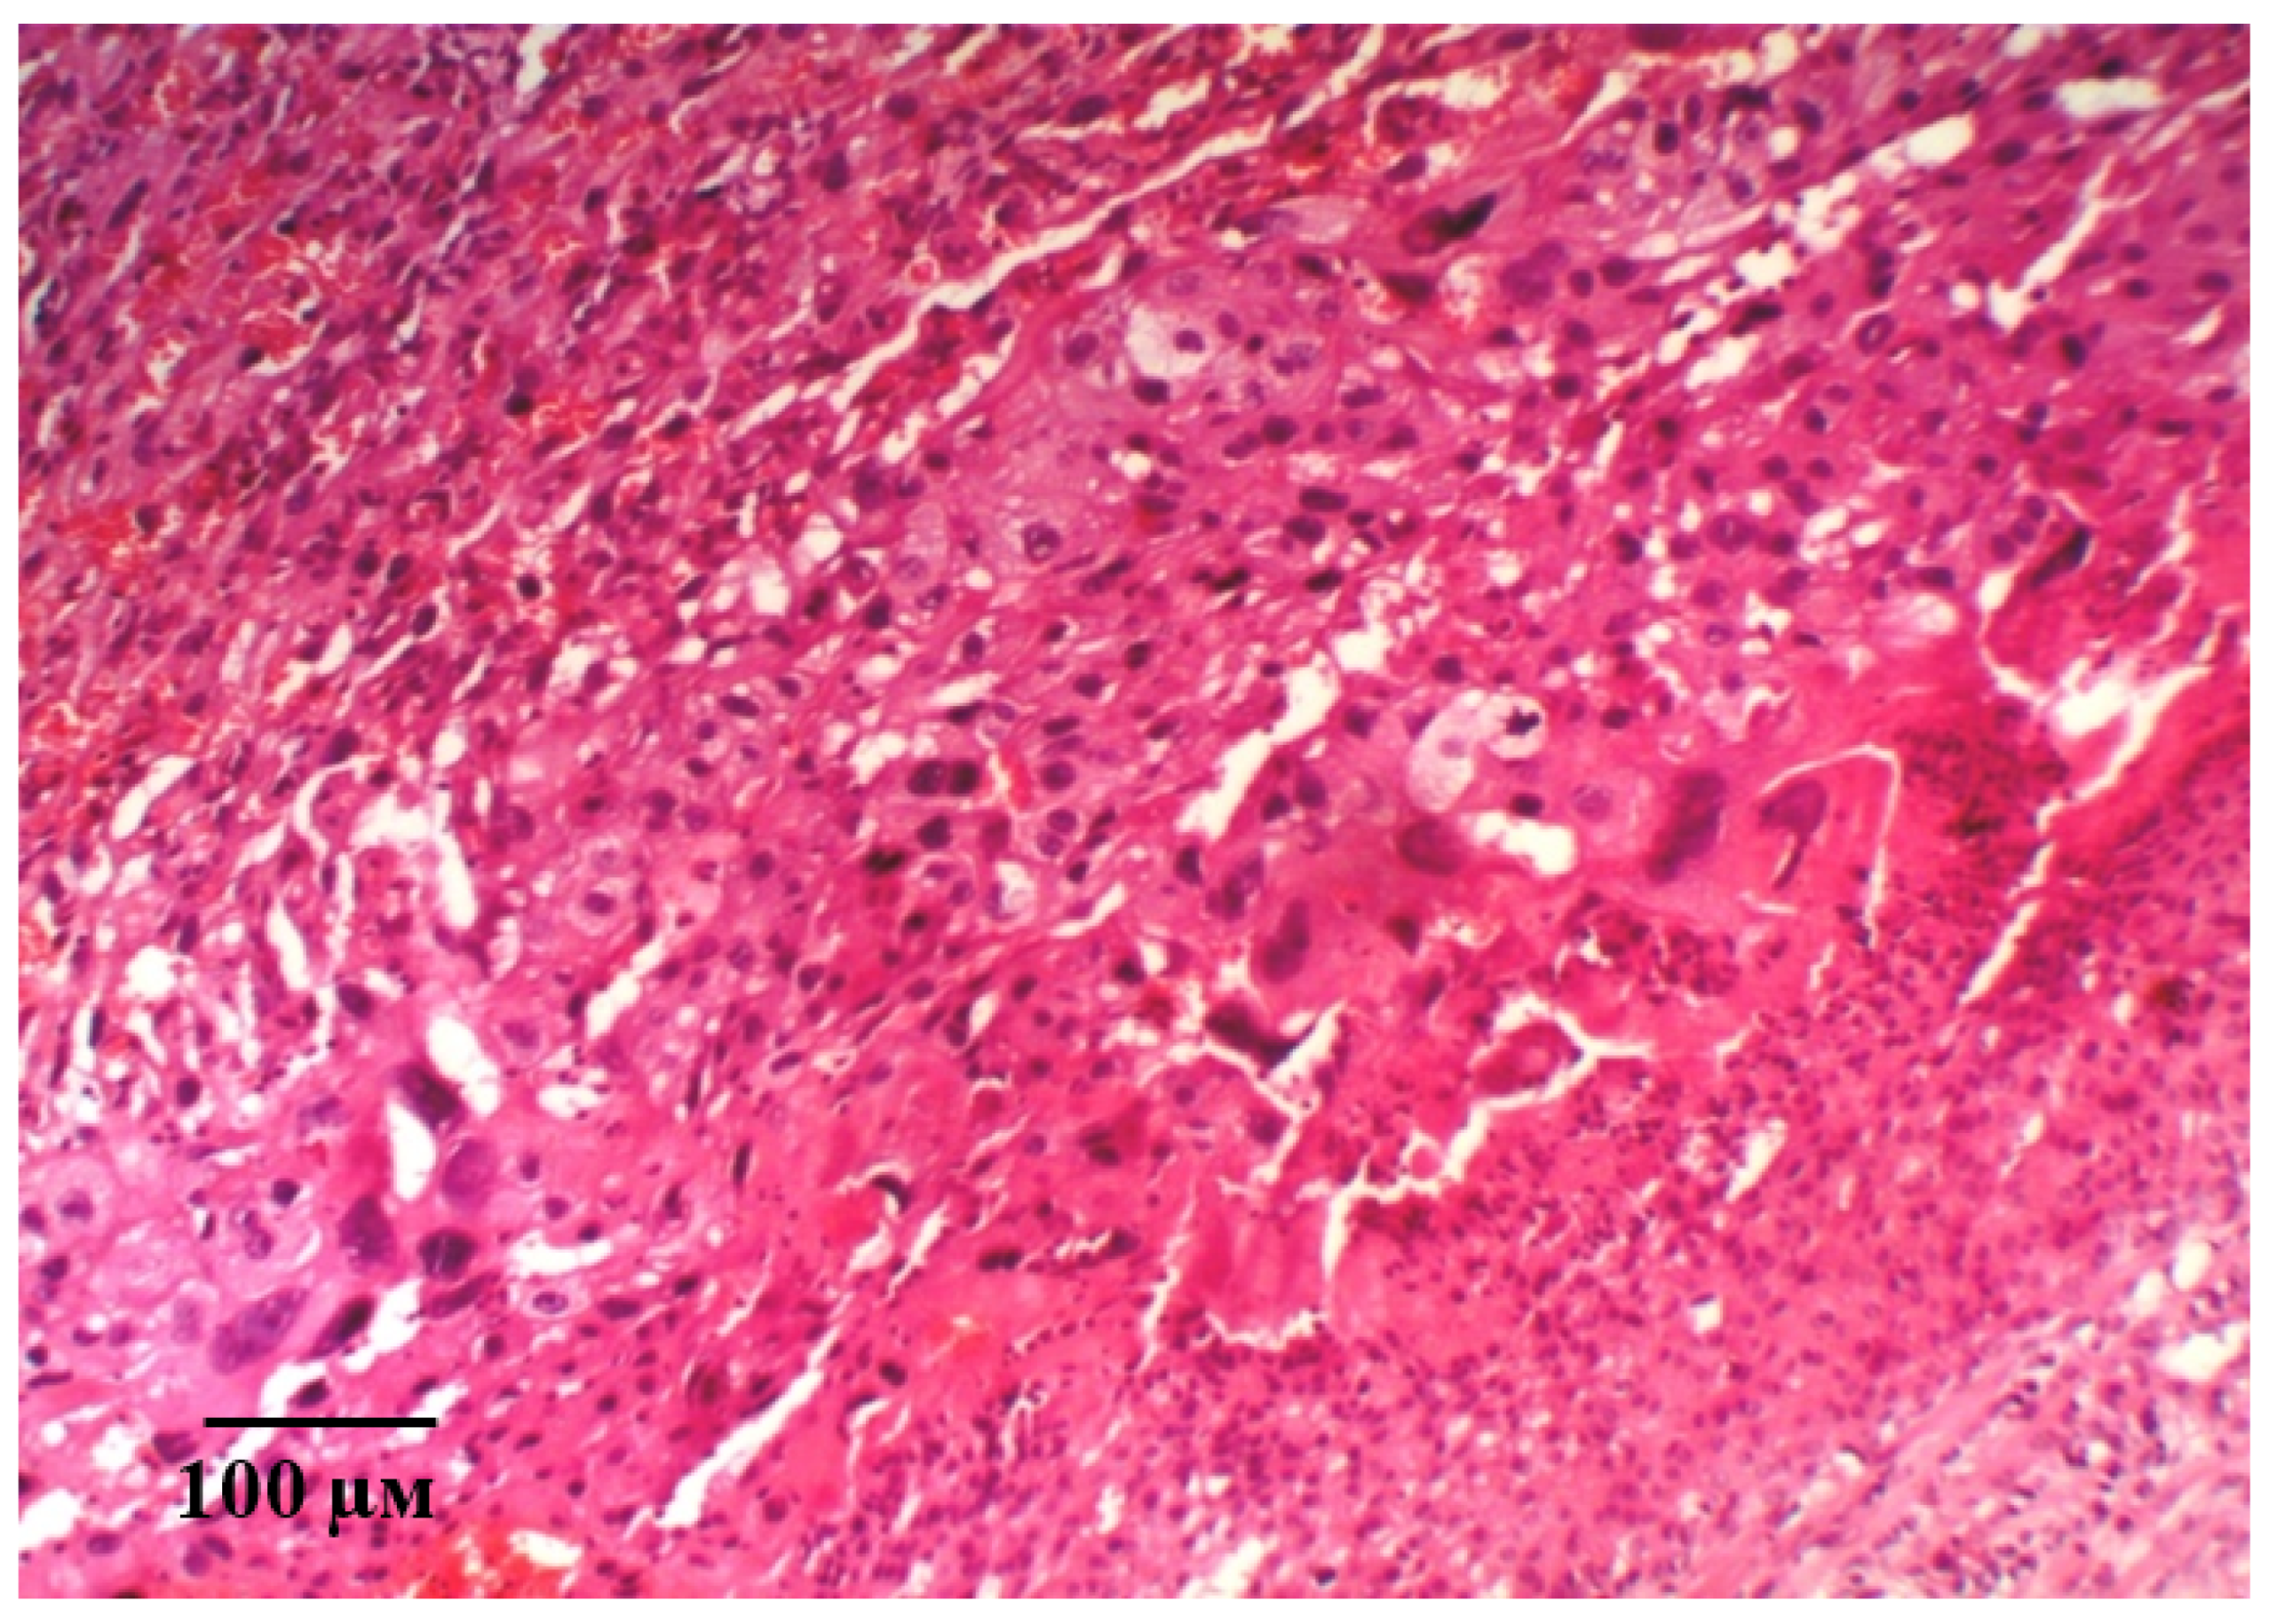

2.2. Results of Histological Examination

| Group | Decidual Cell Density, /0.008 mm2 | Cell Dencity in the Fetal Placenta, /0.008 mm2 | Villi Diameter, ×10−3μm |

|---|---|---|---|

| Int | 114.2 ± 2.03 y | 236.9 ± 2.75 y | 32.18 ± 0.39 y |

| L-NAME | 22.3 ± 0.28 * | 78.5 ± 2.51 * | 16.79 ± 0.24 * |

| Epo (50 IU/kg) | 74.3 ± 0.73 *,y | 137.0 ± 4.17 *,y | 22.33 ± 0.16 *,y |

| pHBSP (10 μg/kg) | 67.7 ± 0.59 *,y | 92.3 ± 1.24 *,y | 21.01 ± 0.16 *,y |

| pHBSP (250 μg/kg) | 80.2 ± 0.75 *,y | 160.0 ± 3.22 *,y | 30.91 ± 0.17 *,y |